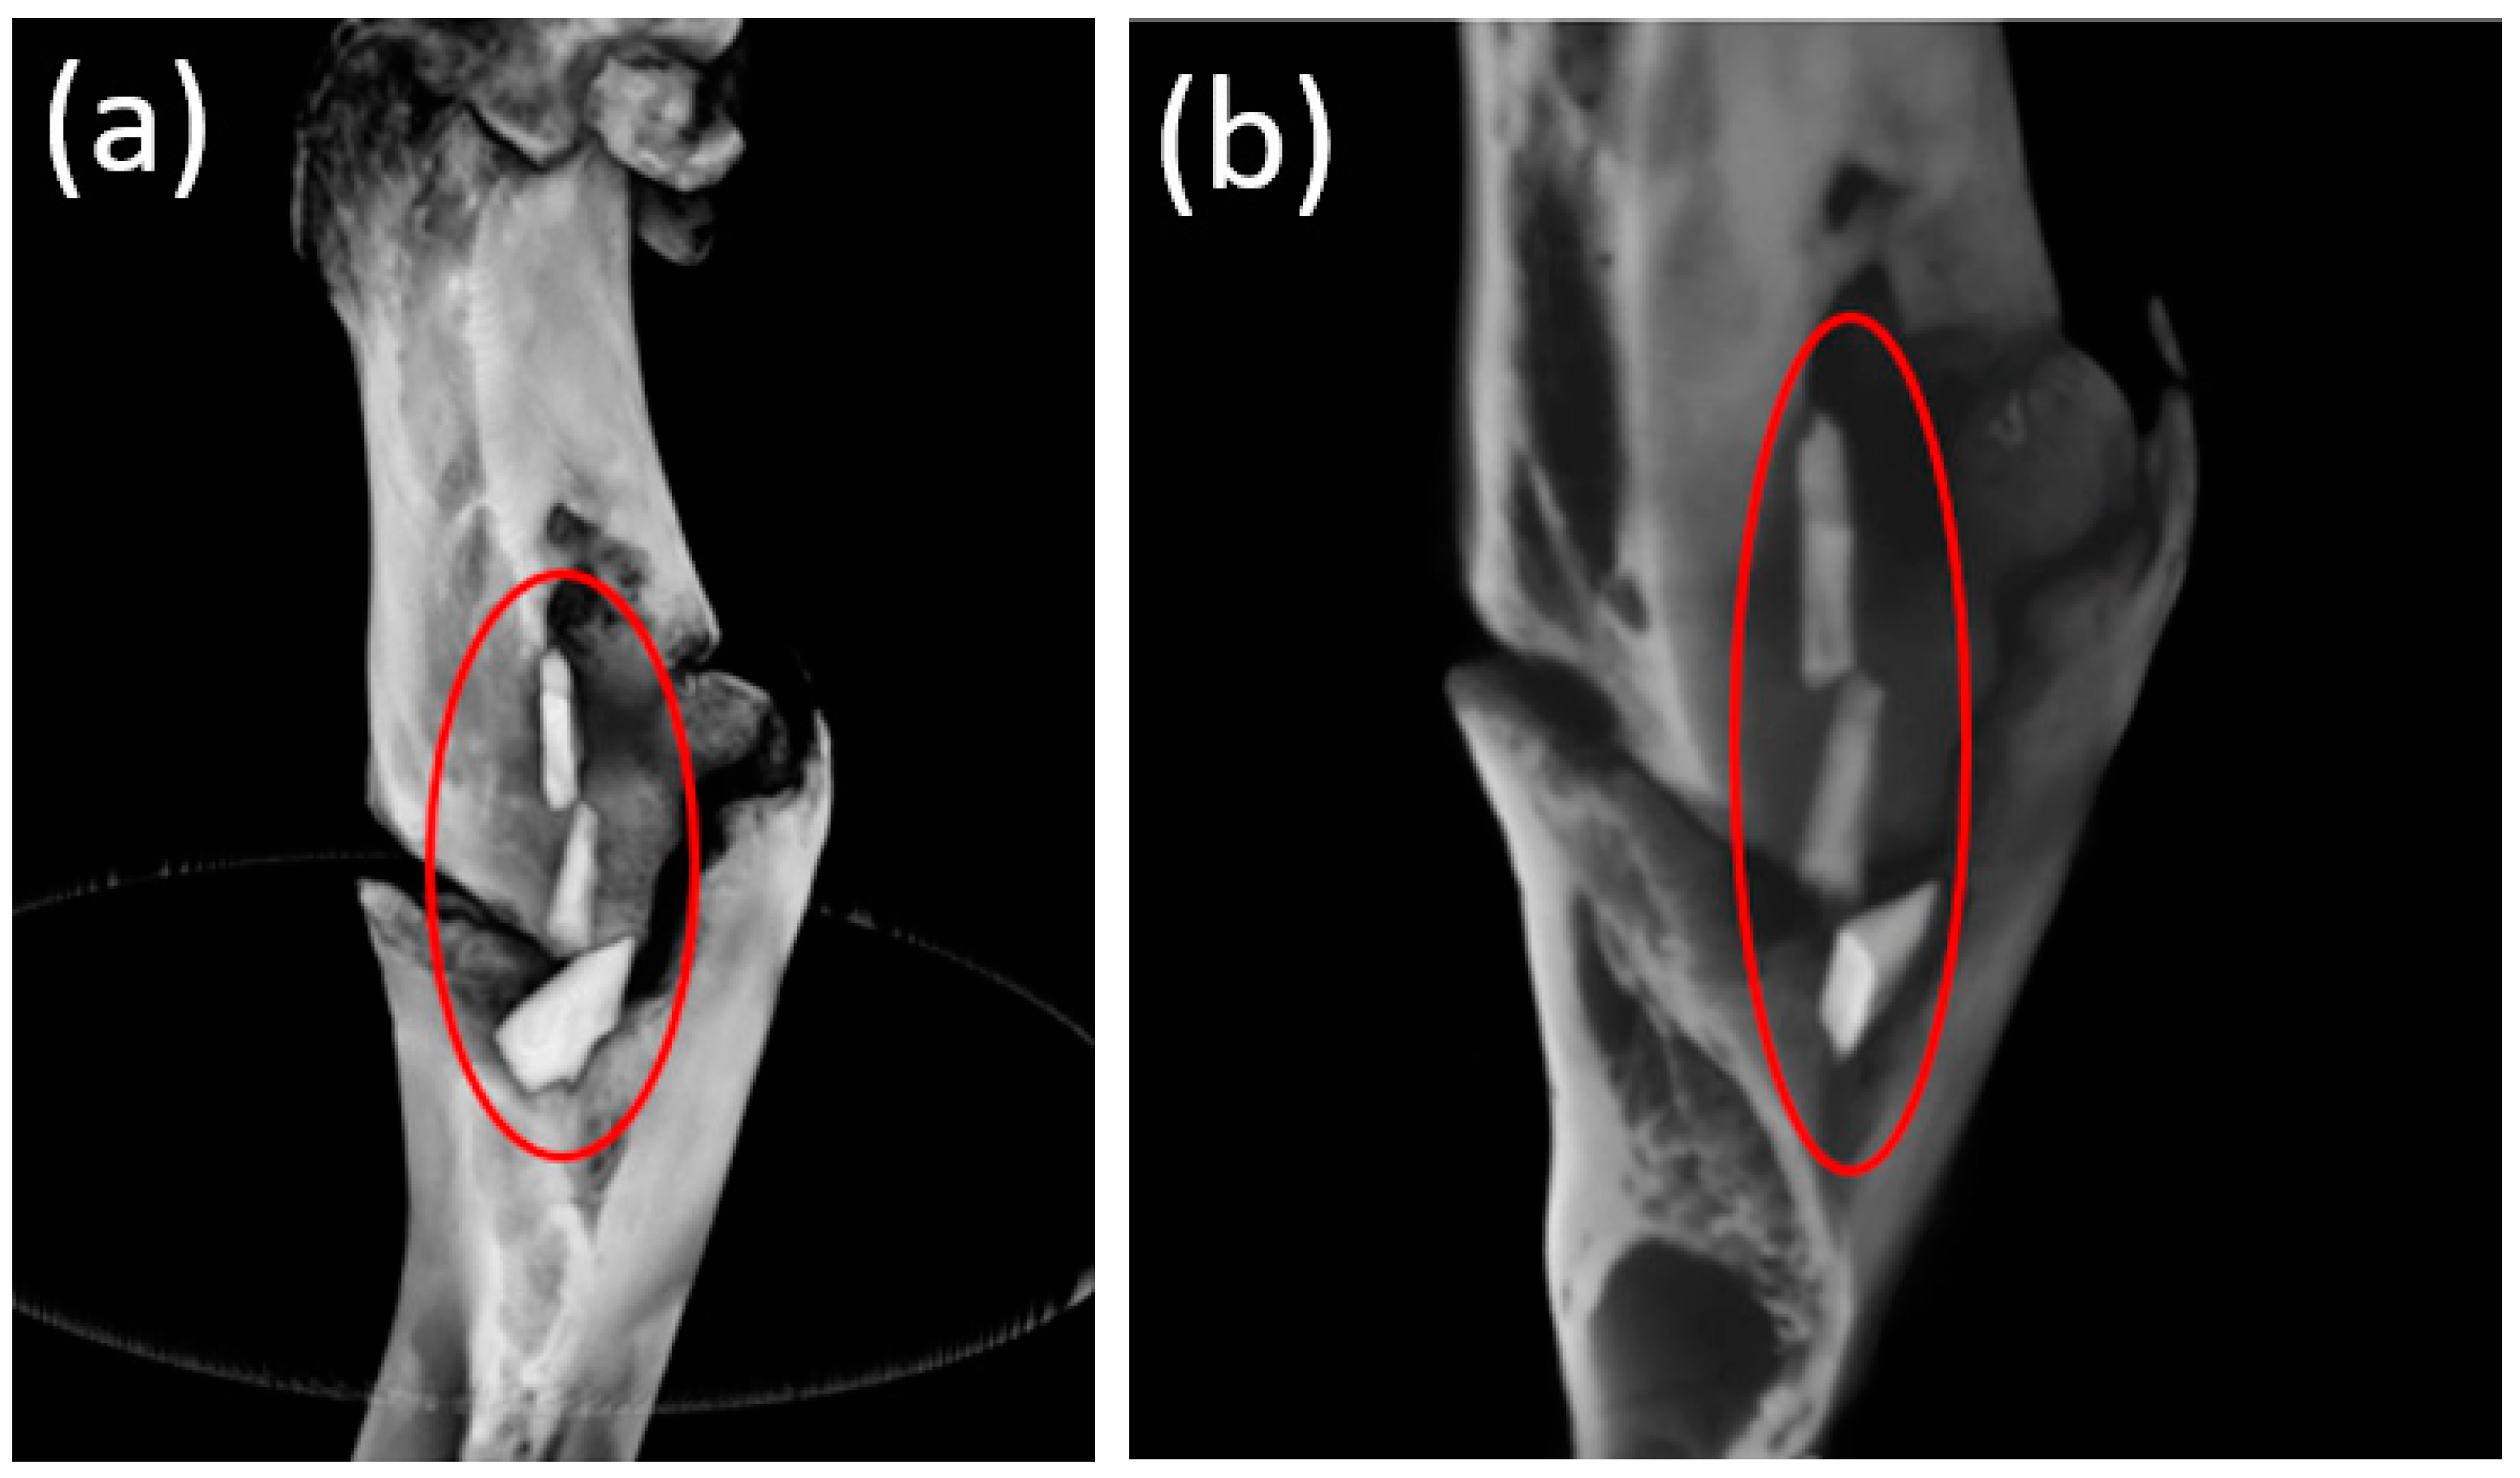

Before an animal was removed from the experiment, an ultrasound study was performed in the femur area to assess the formation of gas cavities from the release of H2 during the magnesium biodegradation. A gaseous layer was visualized in the soft tissues over the area of the installed implants after 3 and 6 months (Figure 6a,b).

Figure 6. Ultrasound data of the postoperative area after (a) 3 months and (b) 6 months. The gas layer in the soft tissues was visualized.